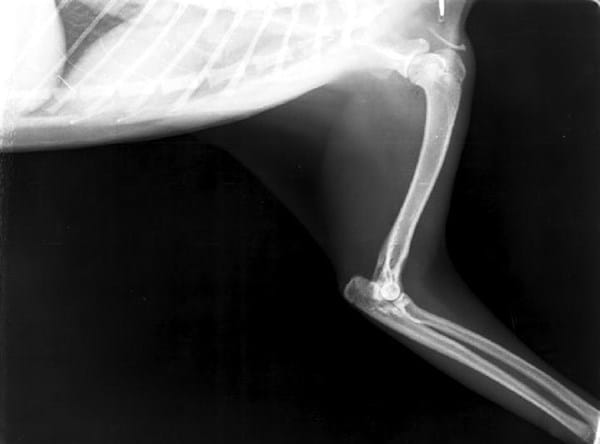

A mi gata de año y medio le han diagnosticado artrosis de cadera y artrosis de codo, también fue diagnosticada con calicivirus hace unos meses. El veterinario que la ha diagnosticado nos aconseja que NO la operemos, y nos recomienda dos opciones de tratamiento: aplicar factores de crecimiento o trasplante de células madre.

El pronóstico que nos ha dado no es demasiado bueno, puesto que el codo izquierdo ya está en bastante mal estado como se ve en las radiografías y las caderas van por el mismo camino, sobretodo la derecha. Además nos comentó que el calicivirus va a hacer que se deteriore todo más rápido.